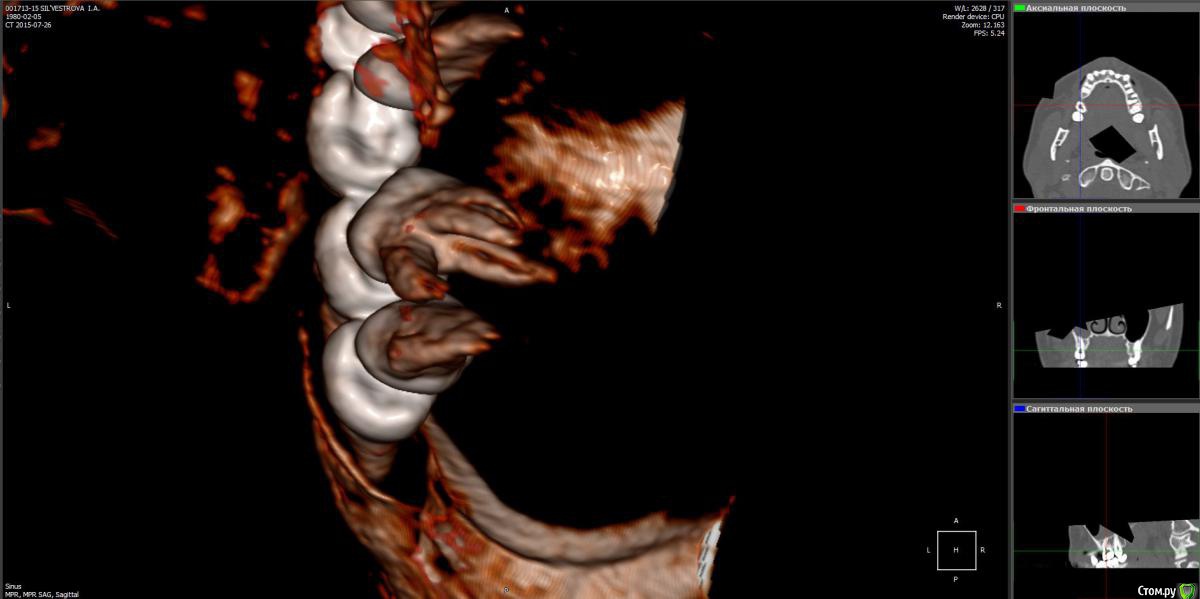

Лисица Опубликовано 26 июля, 2015 Автор Поделиться Опубликовано 26 июля, 2015 (изменено) Вы же не думаете, что Вам назначат а/б терапию по интернету? Я просто не знаю, исходя из каких показателей она назначается. Поэтому осведомилась на всякий случай. Итак, сходила я сегодня на КТ. И по ходу мне сделали что-то не то... Когда я обратилась в клинику, я уточнила, что мне нужно КТ для эндодонтии, чтобы видно было каналы, с достаточным разрешением, чтобы было видно зубы и их корни, входящие в верхнечелюстной синус. Администратор клиники уточнила у врача и сказала, что мне нужно заказывать не КТ верхней челюсти, а КТ пазух. У рентгенолога я также повторила все описанное, рассказала, что при лечении каналов вчера была продырявлена пазуха, уточнила, будут ли видны как следует зубы и их каналы, меня заверили, что "все будет". Причем у врача, судя по описанию на сайте клиники, была ординатура по хирургии в медико-стоматологическом университете, так что он, уж наверное, понимал, что мне нужно. В итоге я получила пленку со снимками формата чуть ли не А3 и диск. На пленке все зубы были просто белыми и коронки видны не целиком. Заключение: в правой верхнечелюстной пазухе уровень жидкости, острый правосторонний гайморит.Думала, может в программе можно будет увеличить разрешение. Но похоже, что нет... или я просто ламер? Зубы просто размытые и белые... Прилагаю сделанные мной скриншоты, как мне кажется, наиболее показательные... Если нужно другие "виды", то скажите какие, или такие снимки вообще ни о чем? Программа просмотра называется Philips DICOM Viewer R3.0-SP03. Аппарат был не местный "на голову", а здоровый, куда заезжаешь в лежачем положении. Изменено 26 июля, 2015 пользователем Лисица Ссылка на комментарий

Лисица Опубликовано 27 июля, 2015 Автор Поделиться Опубликовано 27 июля, 2015 К сожалению, предыдущие сообщения уже не редактируются, но я наконец разобралась с правильным просмотром через DICOM Viewer Теперь у меня есть приличное 3D и я беру обратно свои слова насчет "неправильной" КТ %) Хотя все же нужно было делать челюсти, лобные доли мне как бы совсем ни к чему, а вот нижняя челюсть пригодилась бы...Думаю, как бы выложить DICOM-данные. Ссылка на комментарий

Лисица Опубликовано 27 июля, 2015 Автор Поделиться Опубликовано 27 июля, 2015 Вот что я нарисовала, почти ортопантомограмма Но четкости добиться не выходит все же. Ссылка на комментарий

St. Опубликовано 27 июля, 2015 Поделиться Опубликовано 27 июля, 2015 Гайморит справа есть, и жидкость тоже. Корни этого зуба действительно заканчиваются в гайморовой.Ничего такого страшного, чтоб однозначно удалять зуб я не вижу. С гайморитом - к лорам на лечение.В зубе я бы ещё раз поменяла лекарство на пару недель, пока гайморит не притихнет, потом постоянно пломбировать. 1 Ссылка на комментарий

Лисица Опубликовано 27 июля, 2015 Автор Поделиться Опубликовано 27 июля, 2015 St., большое спасибо за ответ! Моя врач планировала закрыть его в среду (зная о том, что пазуха проткнута). Если запломбировать, пока воспаление есть, какие могут быть проблемы? И еще она сказала, что нащупала 4-й тонкий канал, но не было времени его прочистить, так что она оставила как есть до среды. Сказала, что почистит и сразу же закроет. Судя по КТ, корня 3, значит в одном из них 2 канала? В 3D похоже, что корни с медиальной стороны сросшиеся какие-то... и на небном тоже борозда. Ссылка на комментарий

St. Опубликовано 28 июля, 2015 Поделиться Опубликовано 28 июля, 2015 Пожалуйста!По поводу закрывать или нет - врач на приеме посмотрит если жидкость в каналах и на основании этого примет решение. Да, в одном корне бывает несколько каналов.И не забудьте показать доктору КТ, это облегчает работу. Ссылка на комментарий